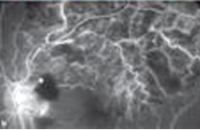

Diabetes can adversely affect the eye, depending on the duration of disease. Diabetes may cause narrowing of the blood vessels, which may cause ischemia, or lack of blood supply to the eye.

This is usually heralded by the sudden onset of blurred vision, which can be total, in case of Central Vein Occlusion, or partial ( in case of branch vein occlusion).